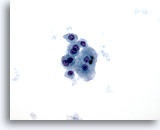

画像 2: 肝FNA – 良性肝細胞

反応性変化を来した良性肝細胞の集塊。細胞境界が明瞭な立方形の細胞が認められます。不透明な細胞質には空胞が認められるものもあれば、幾分顆粒状を呈するものもみられます。辺縁部は擦り切れた状態を呈しています。核はわずかに大小不同で、二核を有する細胞も認められます。小型の核小体がみられます。

40倍

画像 2

肝FNA – 良性肝細胞

反応性変化を来した良性肝細胞の集塊。細胞境界が明瞭な立方形の細胞が認められます。不透明な細胞質には空胞が認められるものもあれば、幾分顆粒状を呈するものもみられます。辺縁部は擦り切れた状態を呈しています。核はわずかに大小不同で、二核を有する細胞も認められます。小型の核小体がみられます。

40倍